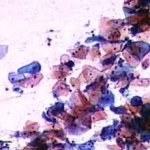

Πινακοθήκη κυτταρολογικών ευρημάτων ΙΙΙ

Οι πινακοθήκες κυτταρολογικών ευρημάτων, έχουν σαν στόχο να εμπλουτίσουν την κυτταρολογική εμπειρία σπουδαστών και ειδικευομένων, όπως ένας άτλαντας.

Παρουησιάζονται λοιπόν τυχαία ευρήματα, από το καθημερινό γυναικολογικό ιατρείο.